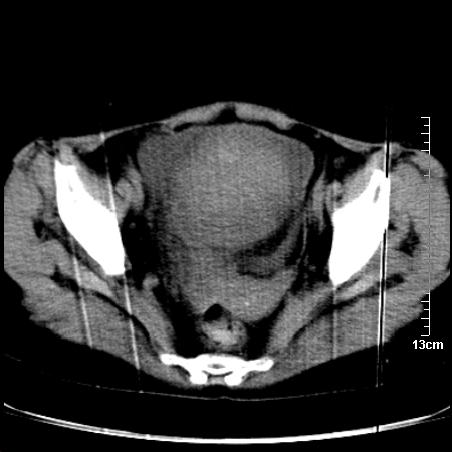

术前的疏忽,手术前诊断阑尾炎,但是没有常规做b超,导致术后1周检查发现 1。实性包块?2。腹腔术后脓肿?

病史:病人一周前诊断阑尾炎,未做b超,手术发现阑尾化脓,(没有留意有无包块),术后1周病人发热,血象:1.6万,做b超发现,随ct检查,上传图片

巨大囊实性包块,边界大部尚清楚,不太像脓肿的表现。应该做个增强检查除外盆腔肿瘤。

脓肿可能性大. 因回盲部区域化脓性兰尾切除残端感染改变征像与实性肿块关系密切.肿块上界至右下腹,下界至盆腔膀胱上缘, 如果是实性肿块在兰尾术中可能就会发现. 所以术后一周病人高烧, 白细胞增高,临床表现支持脓肿.

盆腔一边界大部份清晰囊实性肿块,其周腹脂未见确切异常,其一端与右侧附件相连。考虑右侧附件肿瘤。

如果能进行肠道准备就好了!盆腔内巨大囊实性包块,右前缘与周围肠管分界不清,病灶内前部的气体是否为肠管内气体形成的假象不能确定。

这么大一包快手术当中没有发现?值得怀疑!结合化脓性阑尾炎病史,首先考虑脓肿!不排外附件来源的肿瘤,建议增强扫描!!